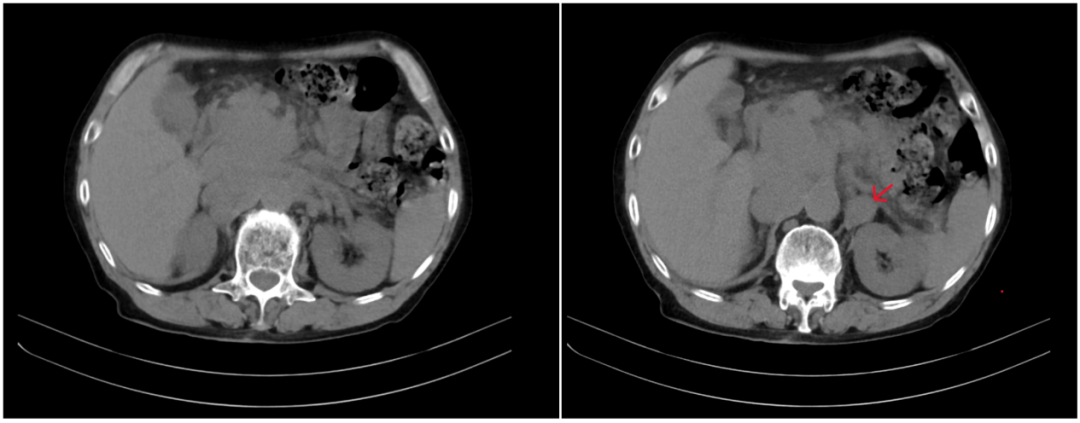

全腹

盆腔CT平扫(2023-06-13):左侧髂血管走行区及腹股沟区多发肿大淋巴结,建议进一步检查。

图1 患者

PET-CT(2023-06-19):1.左侧颈部Ⅰ-Ⅳ区、双侧腋窝、腹腔及腹膜后腹主动脉及下腔静脉周围、肠系膜区、右侧膈脚后、左侧髂外血管区、双侧腹股沟区多发增大淋巴结,部分融合成团,代谢增高,SUVmax约41.1,考虑淋巴瘤可能性大,建议获得病理结果;2.双肺慢性炎症或纤维灶;